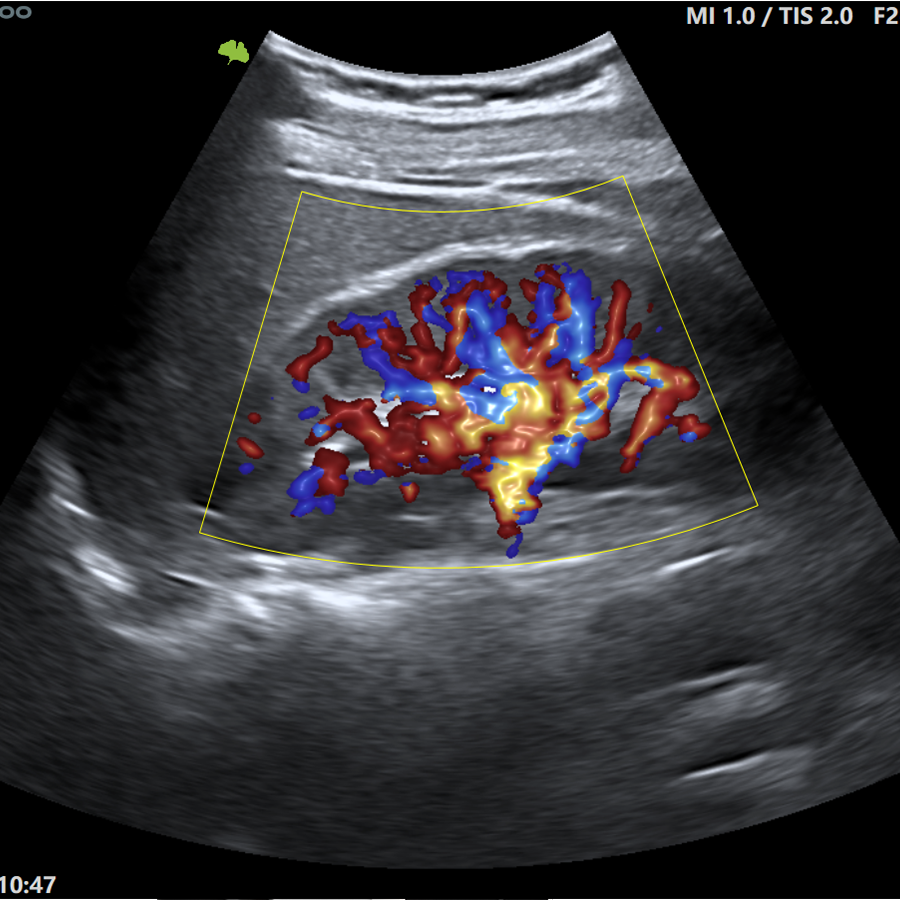

Doppler

- Modo CFM (Color)

- Modo DPI (Power)

- VFlow+

- Doppler 3D